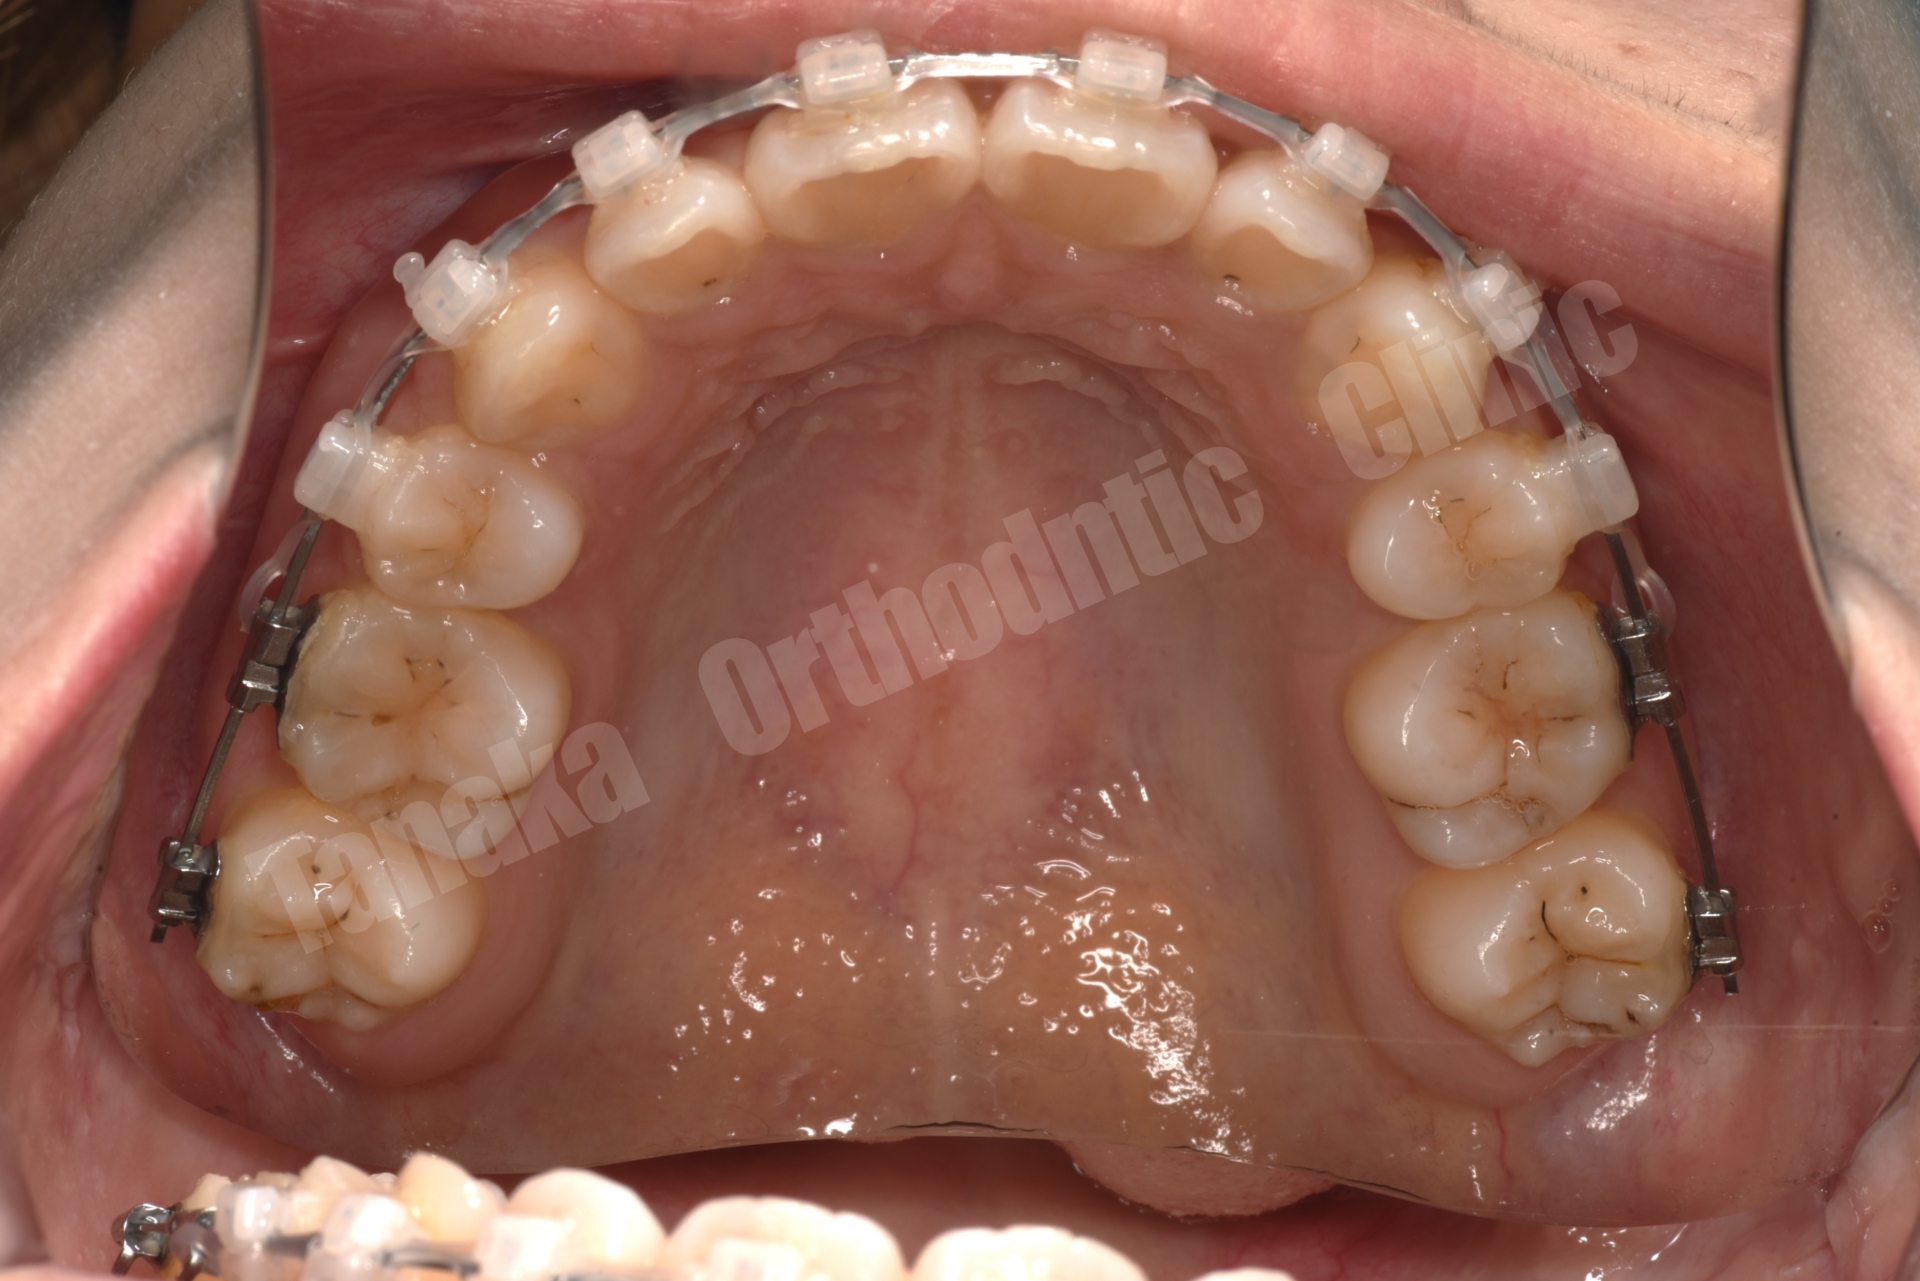

そこで治療では上下歯列に唇側マルチブラケット装置を装着し、歯列全体の排列を行いました。上顎前突を改善するため上顎両側4番を抜歯し、前歯を後退させて口元のバランスを整える計画としました。さらに下顎正中の改善のため右下Eを抜歯し、約11mmある乳臼歯部のスペース閉鎖を行う計画としました。このスペース閉鎖には矯正用アンカースクリューを使用し、右側6番・7番を近心移動させる必要があります。また治療途中で萌出してくる右下7番の位置を適切にコントロールすることも重要なポイントとなります。

結果として歯の移動は順調に進み、約1年8か月で治療を終了することができました。気になっていた上顎前歯の突出感と側貌は改善し、前歯の咬み合わせも回復しました。また右下乳臼歯部のスペースを閉鎖することで、将来的にインプラントなどの補綴処置が必要になる可能性も回避することができました。